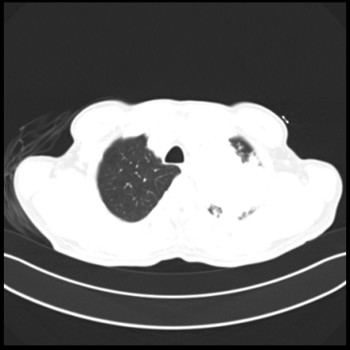

胸部CT示左上肺占位